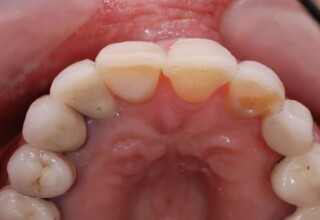

Full mouth prosthetic reconstruction on implants with a different approach on upper and lower jaw

Lower jaw: extractions, direct implant placement and immediate loading (same day) with a transitional bridge.

Upper jaw: Sequential extractions, sequential implant placement and gradual incorporation in the temporary bridge so that the patient was never left without fixed teeth. The aim of the above approach was to have the patient in continuous functional and aesthetic reconstruction, without immediate loading due to anatomical restrictions. Old smiling photos of the patient were used because the natural shape of the teeth was completely lost due to repetitive prosthetic attempts. Tooth relationship and teeth-lip support was transferred to the temporary restorations. Two different transitional bridges were needed to fully estimate phonetics, mastication and esthetics. After the necessary adjustments were finalized, the temporary bridge was used as a guide for the permanent bridges.

Initial

Intermediate

Final